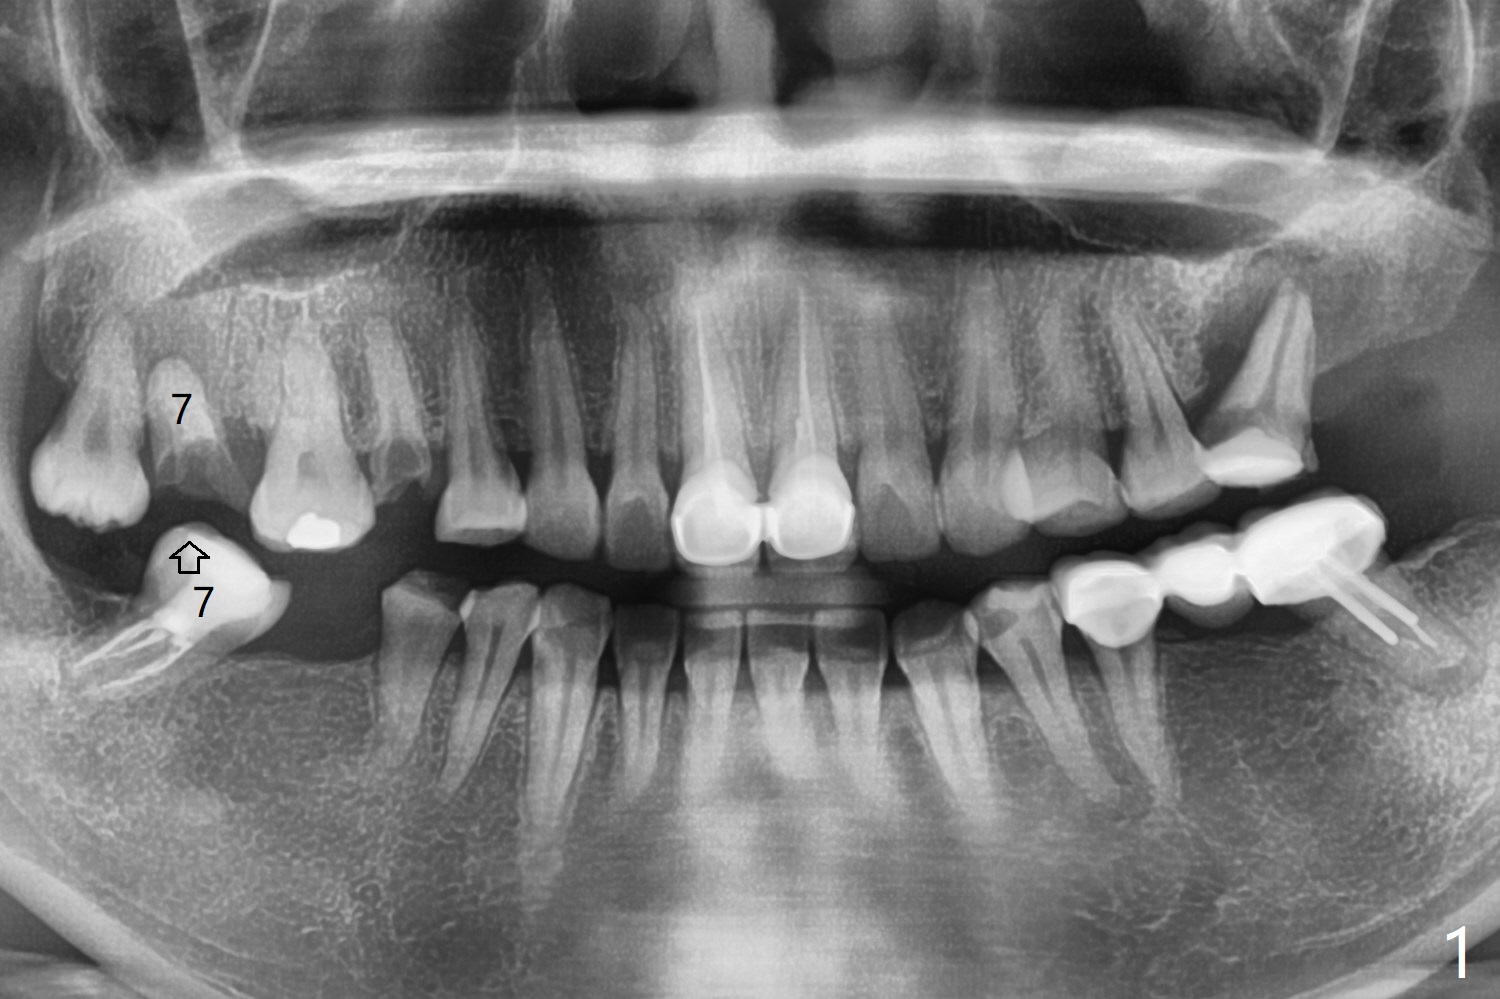

38岁女,牙列不全,咬合塌陷,因右上7疼痛就诊(图一),十分恐惧治疗,虽然残根好像不大,骨粉填入不少(图二:*;使用.5毫升GEM21S,异体骨和合成材料(ß-TCP (beta tricalcium phosphate)),使用不带齿刮匙或者充填器压入牙槽窝。使用GEM Cap(9-12月吸收膜)关闭牙槽窝开口(图三:C),牙周胶水固定膜。由于右下7延申(图一(箭头),四),没有空间放置牙周或者树脂敷料。膜术后4天脱落(加用缝线可以避免早期脱落),7天伤口明显缩小(膜早期脱落好处,图五,与图三对比),白色的骨粉仿佛稳定,所以没有做特殊处理,观察。No Caries GEM21S Xin Wei, DDS, PhD, MS 1st edition 01/26/2021, last revision 02/01/2021